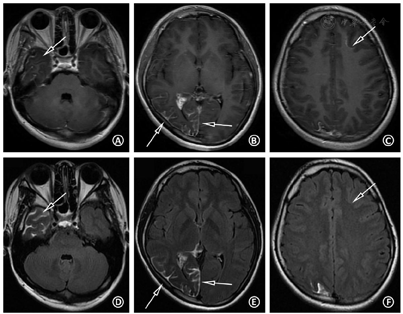

头计算机断层显像(computed tomography,CT)平扫:右侧颅腔、大脑半球较对侧略小,右侧枕颞叶多发斑片状钙化(图4A)。海马常规MRI:右侧海马硬化(图4B)。头颅磁共振静脉血管成像(magnetic resonance venography,MRV):未见明显异常。头增强MRI+SWI:右侧大脑半球体积小,CE-T1序列示右侧颞顶枕叶柔脑膜强化,右侧脉络丛较左侧增大、强化(图4C,图4D,图4E),SWI序列示右侧枕颞叶多发不均匀低信号影,相位图上呈高信号,符合钙化特点(图4F,图4G)。头正电子发射断层显像(positron emission tomography,PET)/CT:右侧颞顶枕叶体积小,脑实质萎缩,代谢减低或缺损,考虑致痫灶定位于右侧半球(图4H)。值得注意的是,CE-T1序列所示右侧颞极(图5A箭头)及左侧额叶高信号(图5C箭头)是否为异常柔脑膜强化不肯定,然而头CE-FLAIR序列可清晰显示右侧颞极存在柔脑膜强化(图5D),并除外左侧额叶的柔脑膜受累(图5F),提示患者的脑膜受累范围为单侧颞顶枕叶广泛受累。结合CE-T1、CE-FLAIR,以及SWI序列(未展示该层面SWI图像),考虑左侧额叶高信号(图5C箭头)为发育性静脉畸形可能。眼科视野检查示双眼左侧视野缺损。皮肤科会诊考虑右侧面部鲜红斑痣临床诊断明确,符合SWS皮肤表现。

此外,对于行癫痫术前评估的SWS患者,明确患侧脑部具体的病变范围,以及除外看似正常的"健侧"脑部的轻微受累,对制定后续治疗方案是不可或缺的。Griffiths等[8]报道了1例疑似左侧SWS的患儿,CE-T1序列仅提示左侧大脑半球异常强化,但CE-FLAIR序列显示对侧柔脑膜亦存在病变,双侧受累排除了手术的可能。对于本例患者,CE-FLAIR序列清晰地显示了右侧颞极等处在CE-T1序列上显示欠清的病变,同时除外了左侧大脑半球受累,从而精确地显示了患者病变的范围。如果仅根据患者CE-T1序列的图像,则可能误认为本例患者右侧脑叶受累范围较小,从而可能作出推荐患者手术治疗的决策,增大患者治疗的风险。